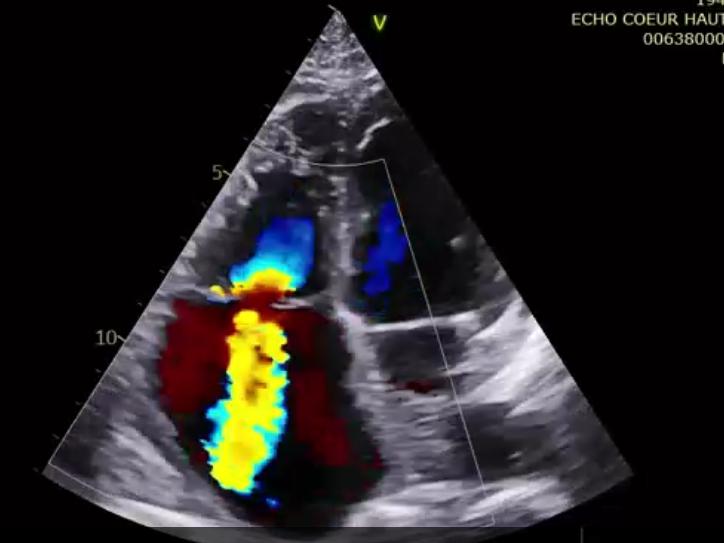

術(shù)前超聲提示極大量三尖瓣反流